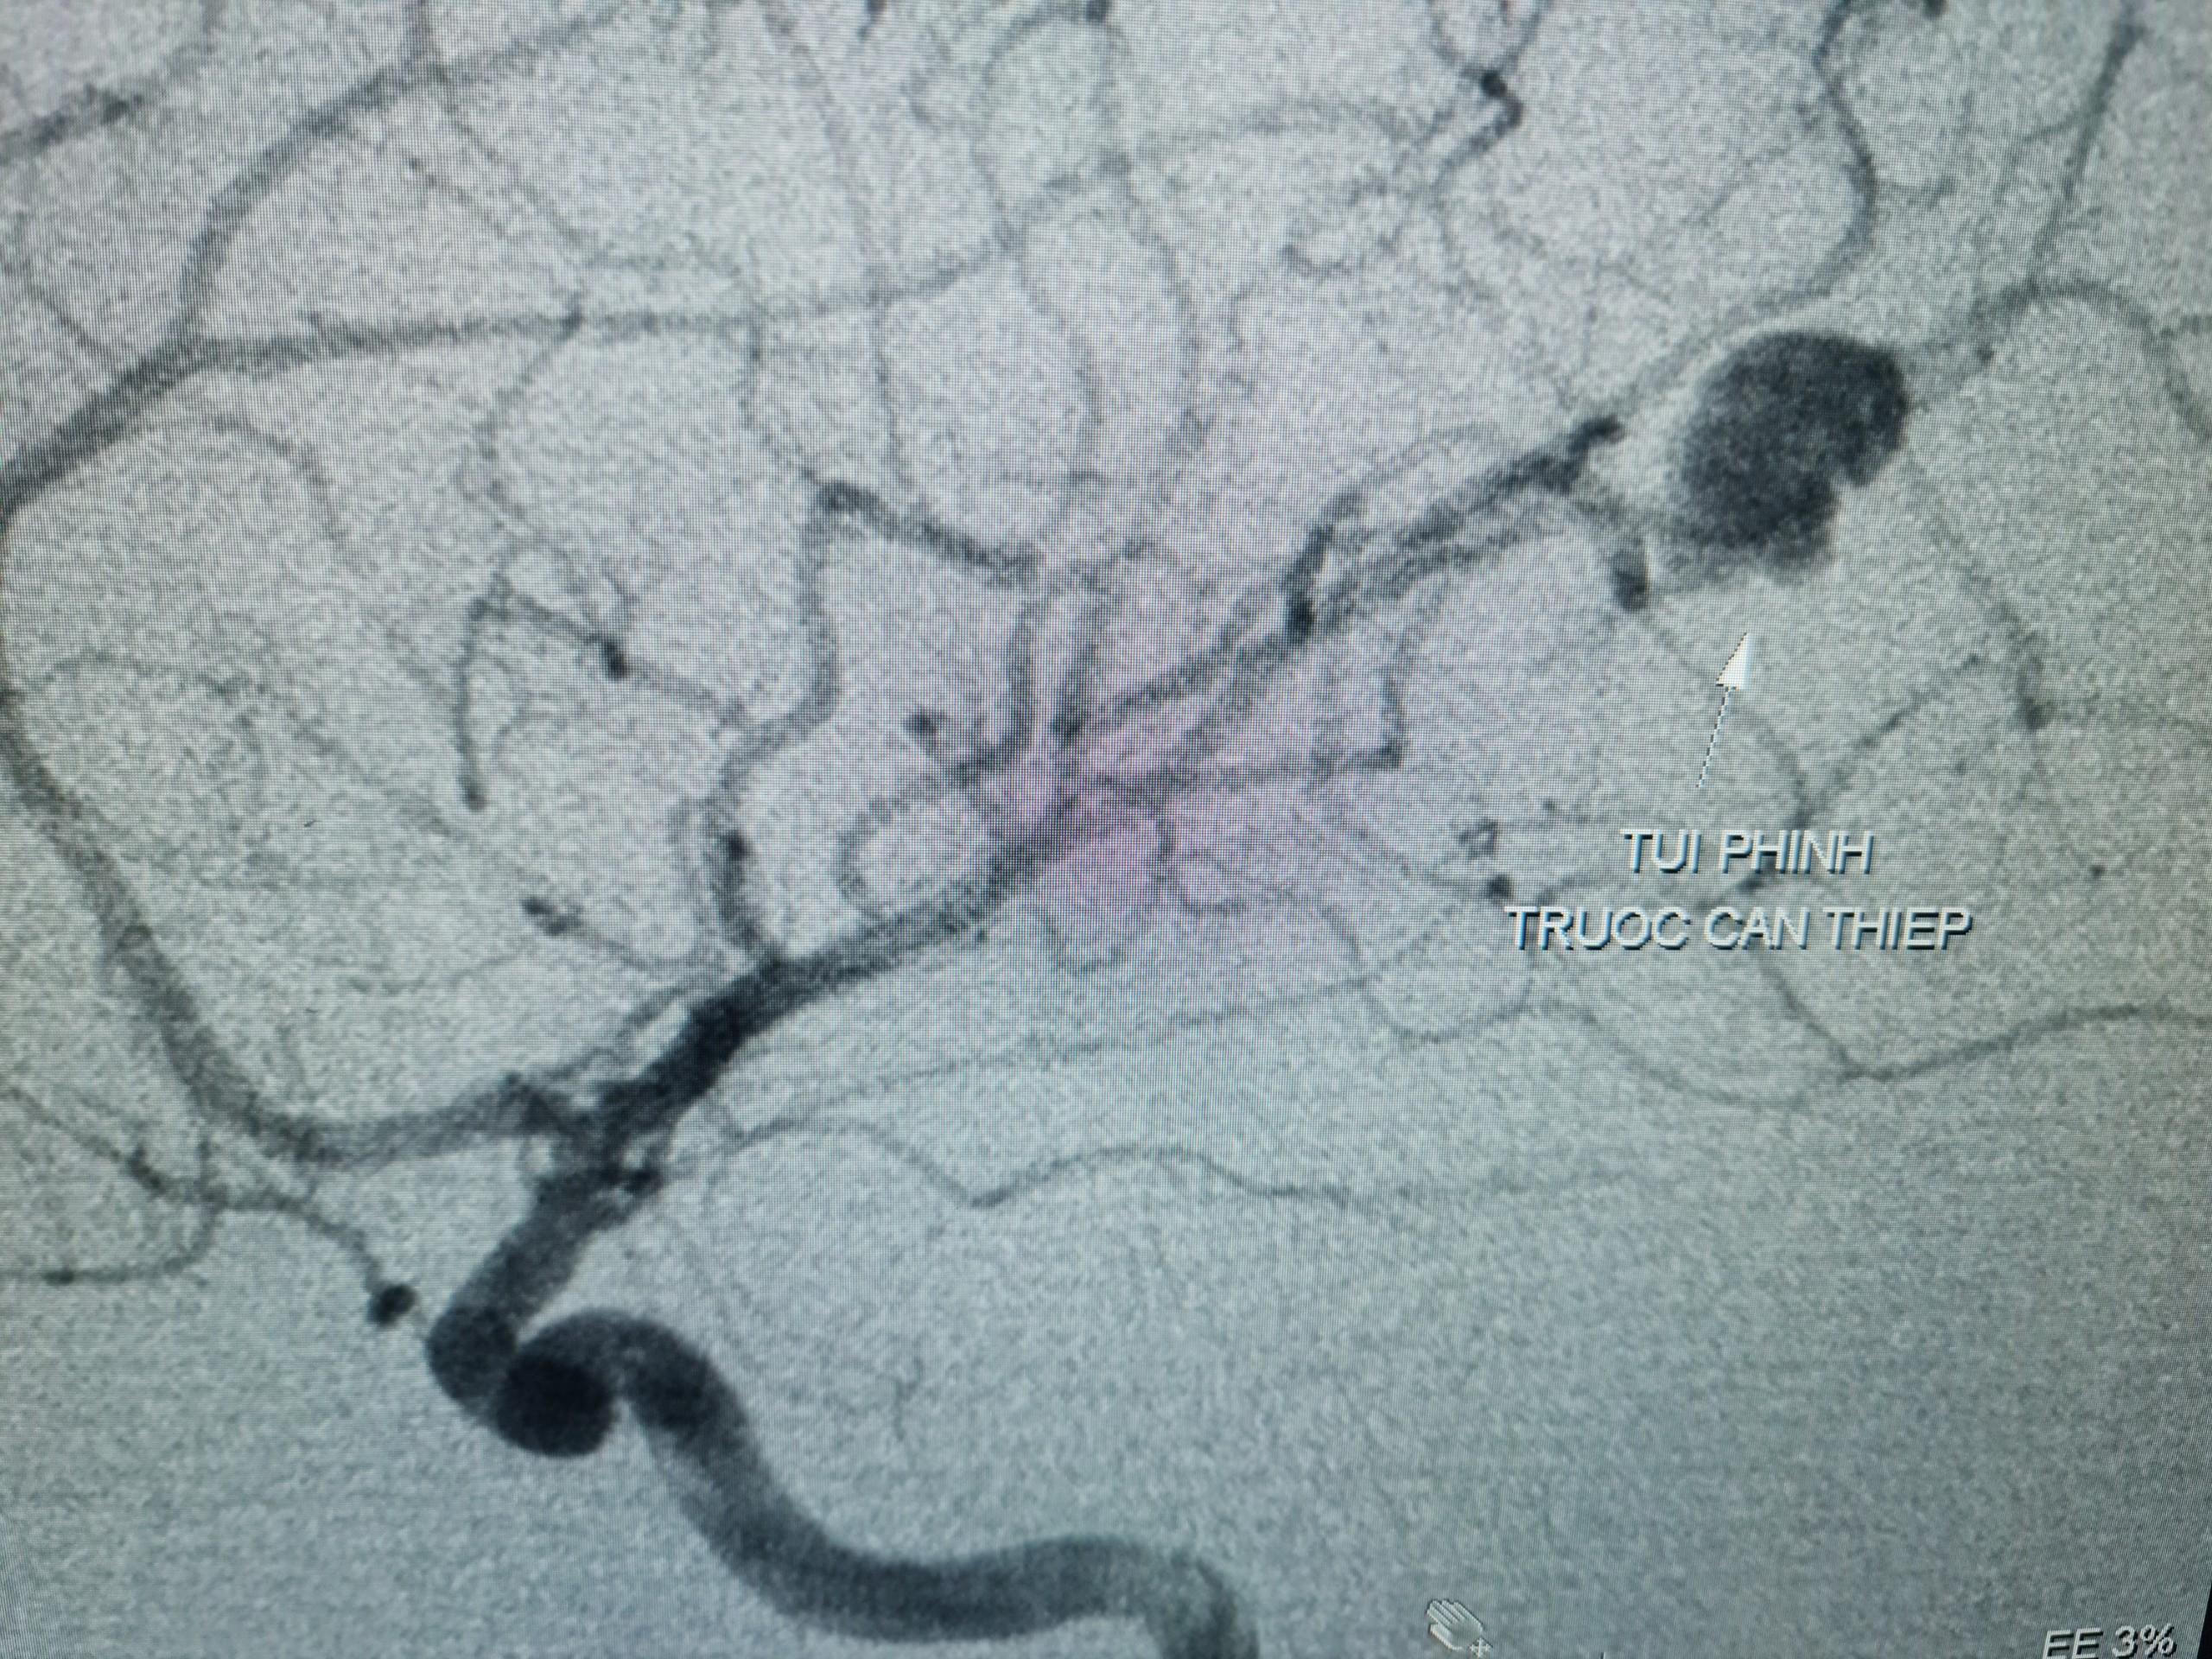

![]() |

Hình ảnh túi phình mạch máu não trước can thiệp |

Các bác sĩ đã quyết định chụp mạch máu não bằng kỹ thuật DSA (chụp mạch máu kỹ thuật số xóa nền) để chẩn đoán xác định. Kết quả chụp cho thấy tình trạng xuất huyết não ở bé là do túi phình mạch máu não vỡ. Bệnh nhân được chỉ định nút phình mạch máu não số xóa nền DSA. Quá trình can thiệp đã diễn ra khá thuận lợi và bít được hoàn toàn túi phình. Hiện bé đã ổn định, hết nhức đầu, ăn uống lại tốt.